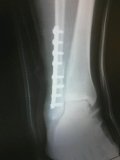

Well this is a blog I never foresaw writing. As of Tuesday the 21st I broke my ankle and have since had surgery, a plate, and 8 screws. I’m not really in any pain but with just one week out from launch I am really worried about what this means for the World Race. I know this didn’t surprise God but it definitely surprised me. And dang it, my last blog was on my reality vs. my expectations and wouldn’t you know it something like this happens.

Just to let everyone know exactly what happened. I was hanging out with my brother in Dallas and we had the bright idea to going to this place with trampolines from wall to wall, they were even leaning up against the wall. I had it in my head that I wanted to do a back flip off a trampoline leaning against a wall and within 10 jumps I had a busted ankle. I remember looking at my ankle and just saying, “it can’t be broke, I have a mission trip to go to, this doesn’t make sense!”